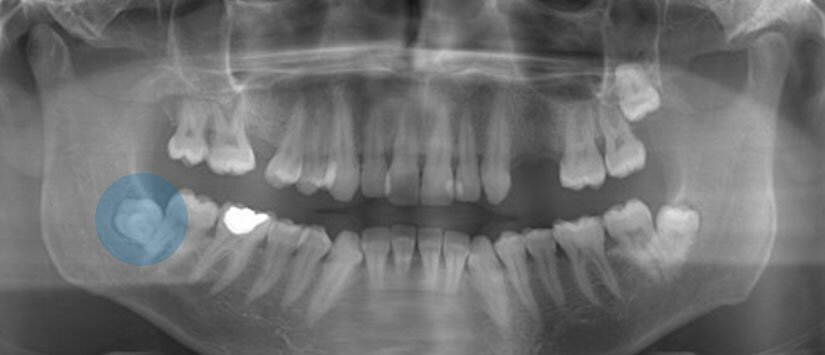

Çocuklarda diş değişimi genellikle 11-12 yaşlarında son bulur ve ağızdaki tüm süt dişleri değişir. Dişlerin değişme sürecindeki bazı aksaklıklar bazen dişlerin sürme zamanlarını geciktirebilir, bazen de daimi dişler gömülü kalabilir. Gömülü dişler, çoğu zaman tel tedavisiyle sürdürülebilmektedir. Bunun için önce tel tedavisine başlanır. Gömülü dişlerin sürdürülmesindeki ilk adım, gerekli diş boşluklarının açılmasıdır. Yeterli boşluklar açıldıktan sonra eğer dişlerin uçları ağızda görülüyorsa, üzerlerine buton ya da ataçman denen parçalar yapıştırılır. Eğer dişler tam olarak gömülü ise cerrahi olarak dişin üzeri açılır ve buton yapıştırılır.

Gömülü dişlerin hareket hızı yaklaşık olarak ayda 2 milimetre civarındadır. Dişler ağız ortamına sürdükten sonra buton sökülerek dişe uygun braket yapıştırılır ve diğer dişlerle birlikte düzeltilir. Tüm gömülü dişlerin sürdürülmesi bazı durumlarda mümkün olamamaktadır. Dişlerin çene kemiklerinin içerisindeki açıları belli değerin üzerinde ise gömülü dişler hareket etmemektedir. Bu durumda dişler cerrahi olarak çekilir ve boşluk konusunda ne yapılacağı tekrar planlanır. Bu boşluklar, ortodontik diş hareketi ile kapatılabilir, ya da bir dişin sığabileceği kadar yer açılıp implant yapılabilir.